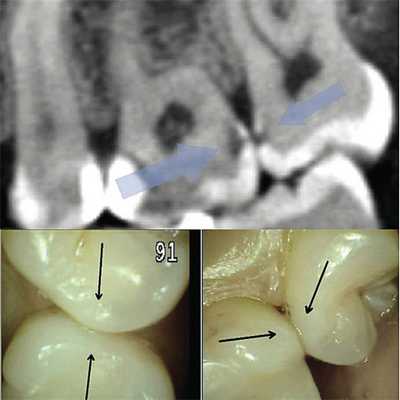

(Слева) На периапикальных рентгенограммах визуализируются четко очерченный рентгенонегативный тракт проводника зу6а (ПЗ) связанный с верхним краем коронки постоянного клыка нижней челюсти справа, мигрировавшего на противоположную сторону. Тракт доходит до альвеолярного гребня возле оставшегося временного клыка справа.

(Справа) На корональной (справа) и аксиальной (слева) КЛКТ визуализируется ПЗ, идущий от коронки импактного постоянного клыка нижней челюсти справа до альвеолярного гребня с язычной стороны от сохранного временного клыка.

2. Рентгенография проводника зуба:

• Интраоральная рентгенография:

о Четко отграниченный рентгенонегативный тракт, идущий от коронки импактного зуба до обычной области прорезывания в альвеолярном отростке

3. КТ проводника зуба:

• КЛКТ:

о Гиподенсный тракт с кортикальной пластинкой, идущий от зубного фолликула импактного зуба до альвеолярного отростка